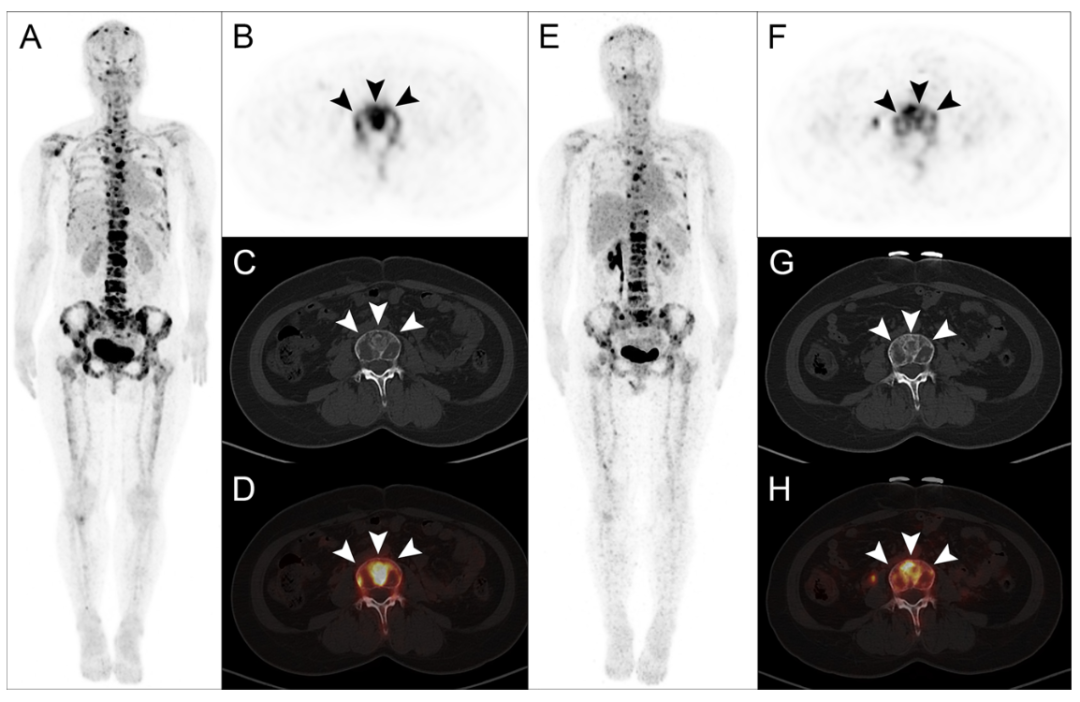

一位33歲的乳(ru)腺癌骨(gu)轉移(yi)患者(zhe)(zhe)在(zai)(zai)接受了1850 MBq的177Lu-DOTA-IBA治(zhi)(zhi)療后(hou),其疼痛(tong)癥狀(zhuang)在(zai)(zai)短(duan)短(duan)一周(zhou)(zhou)內便得到了完全緩(huan)解(jie),而(er)其Karnofsky表現(xian)狀(zhuang)態(KPS)評分也在(zai)(zai)兩周(zhou)(zhou)后(hou)升至(zhi)100分。在(zai)(zai)治(zhi)(zhi)療后(hou)的8周(zhou)(zhou)隨(sui)訪(fang)中,通過68Ga-DOTA-IBA PET/CT影(ying)像復(fu)查發現(xian),該患者(zhe)(zhe)的骨(gu)轉移(yi)病(bing)灶示(shi)蹤劑(ji)攝取(qu)量顯著下(xia)降,SUVmax值(zhi)從治(zhi)(zhi)療前的高水平降至(zhi)10.2,綜合(he)影(ying)像學(xue)與臨床表現(xian),該患者(zhe)(zhe)的治(zhi)(zhi)療效果被(bei)評定為部分反(fan)應(PR),這一結果印證(zheng)了177Lu-DOTA-IBA在(zai)(zai)緩(huan)解(jie)疼痛(tong)、提升生活(huo)質量方面(mian)的卓越能力,彰顯了其在(zai)(zai)促進骨(gu)轉移(yi)病(bing)灶修復(fu)、改善患者(zhe)(zhe)預(yu)后(hou)方面(mian)的巨大潛力。